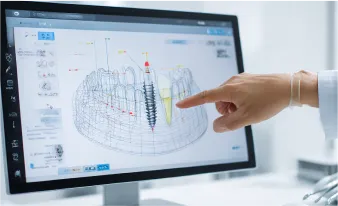

事前準備が重要

精密検査

に基づくインプラント手術

当院ではインプラント手術の前に精密検査を行い、

患者様が安心して手術に挑める環境に努めています。

- シミュレーション